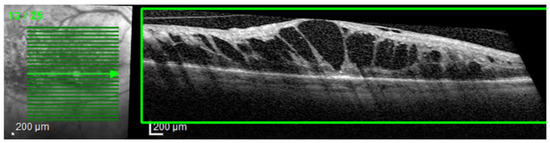

The most common image artifacts observed were distortions and image noise. All images were included in the analysis, without having any external image adjustments or quality enhancers, in order to emulate “real world” everyday clinical practice conditions (see Figure 2 and Figure 3).

Figure 2.

Image distortion. Observe the rhomboid aspect of the image slice (green box) giving the sense of a scan from an angle rather than a perpendicular scan to the retina’s base. This artifact is probably due to a sudden and rapid movement of the eye during scanning.